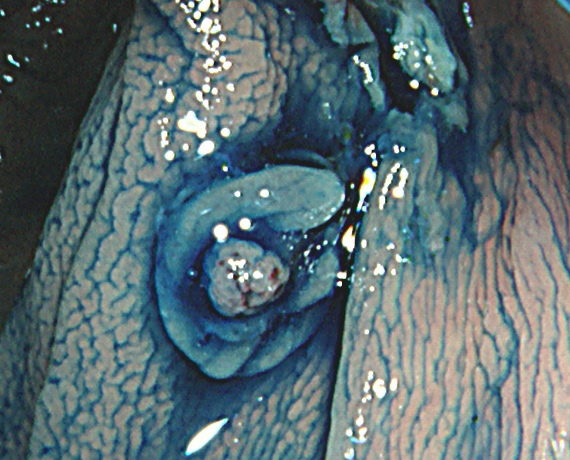

Extended Cold法法で切除された検体は「目玉焼き」のようになります。「黄身」が病変で、「白み」が周囲の正常組織(余白、マージン)です。

腫瘍の取り残しを防ぐために「白み(余白)の大きな目玉焼き」にすることが、最大のポイントです。